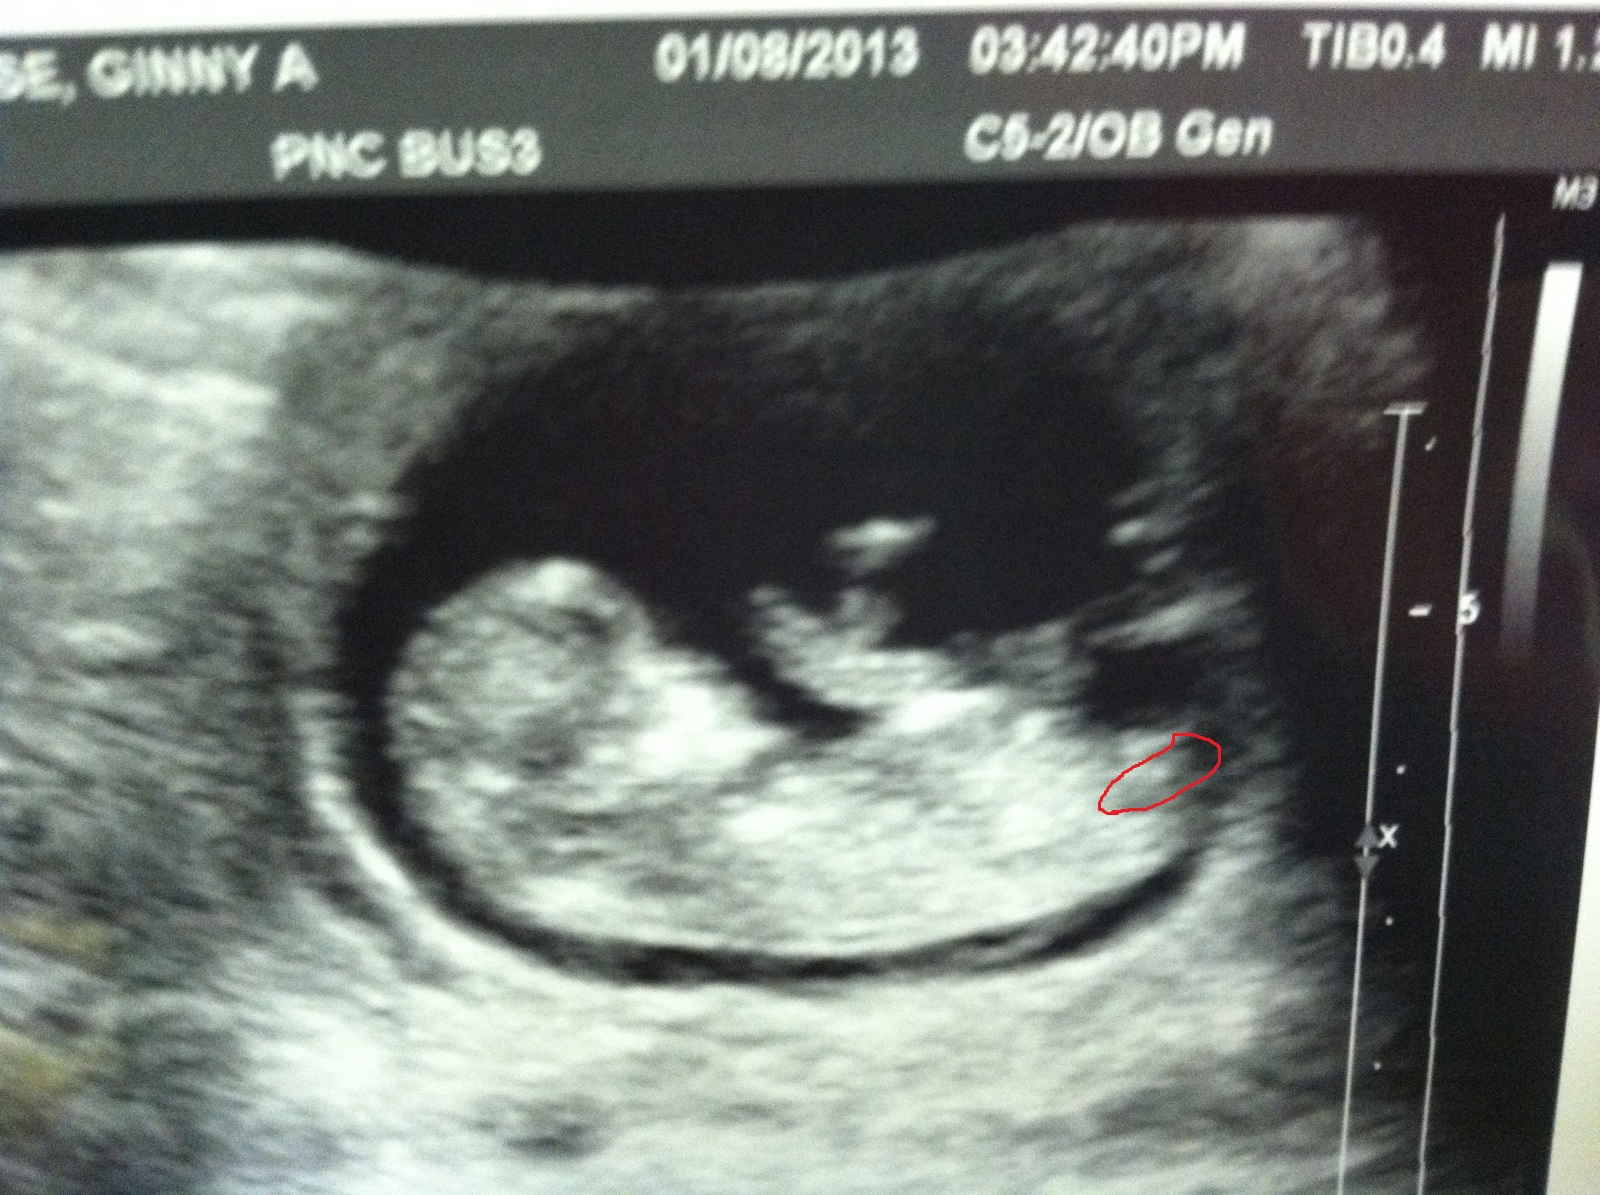

11 week scan. Any gender guesses?!?!?!?

Any chance of posting it again without the red, I feel it's blocking the overall view.

Also, I find out for sure on 2/15. I went last week (15 weeks) and tech said if she had to guess she would say girl, but there were a few views that could have been boy parts. I have 2 girls @ home and this is my last, so I am hoping for a baby boy :-)

i woula guessed girl based on nub but at 11 weeks could be too early and still rise.